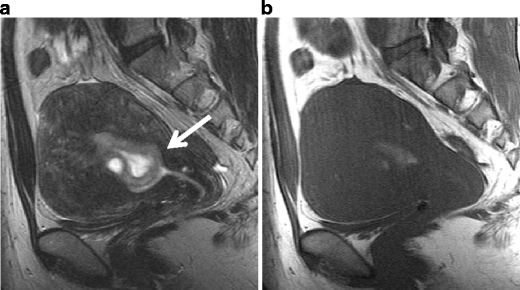

Endometrioid carcinoma in a 30-year-old woman. a Sagittal T2-weighted image demonstrates an ill-defined area of decreased intensity in the thickened endometrium (arrows). b Postcontrast T1-weighted image demonstrates poorly enhanced tumor in the endometrium (arrows). In both images, the endometrial-myometrial border is well preserved, suggesting the tumor is confined within the endometrium

Endometrioid carcinoma in 53-year-old woman. a Sagittal T2-weighted image demonstrates an ill-defined endometrial tumor. The endometrial-myometrial border is almost entirely obscured, suggesting the myometrial invasion by the tumor. b Early-phase image of dynamic enhanced T1-weighted clearly demonstrates inner myometrium of strong enhancement (arrowheads), which become irregular by invading tumor